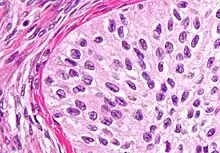

High magnification micrograph of a Brenner tumor, a type of surface epithelial-stromal tumor. H&E stain.

Brenner tumor

Brenner tumors are uncommon surface-epithelial stromal cell tumors in which the epithelial cell (which defines these tumors) is a transitional cell. These are similar in appearance to bladder epithelia. The tumors may be very small to very large, and may be solid or cystic. Histologically, the tumor consists of nests of the aforementioned transitional cells within surrounding tissue that resembles normal ovary. Brenner tumors may be benign or malignant, depending on whether the tumor cells invade the surrounding tissue.